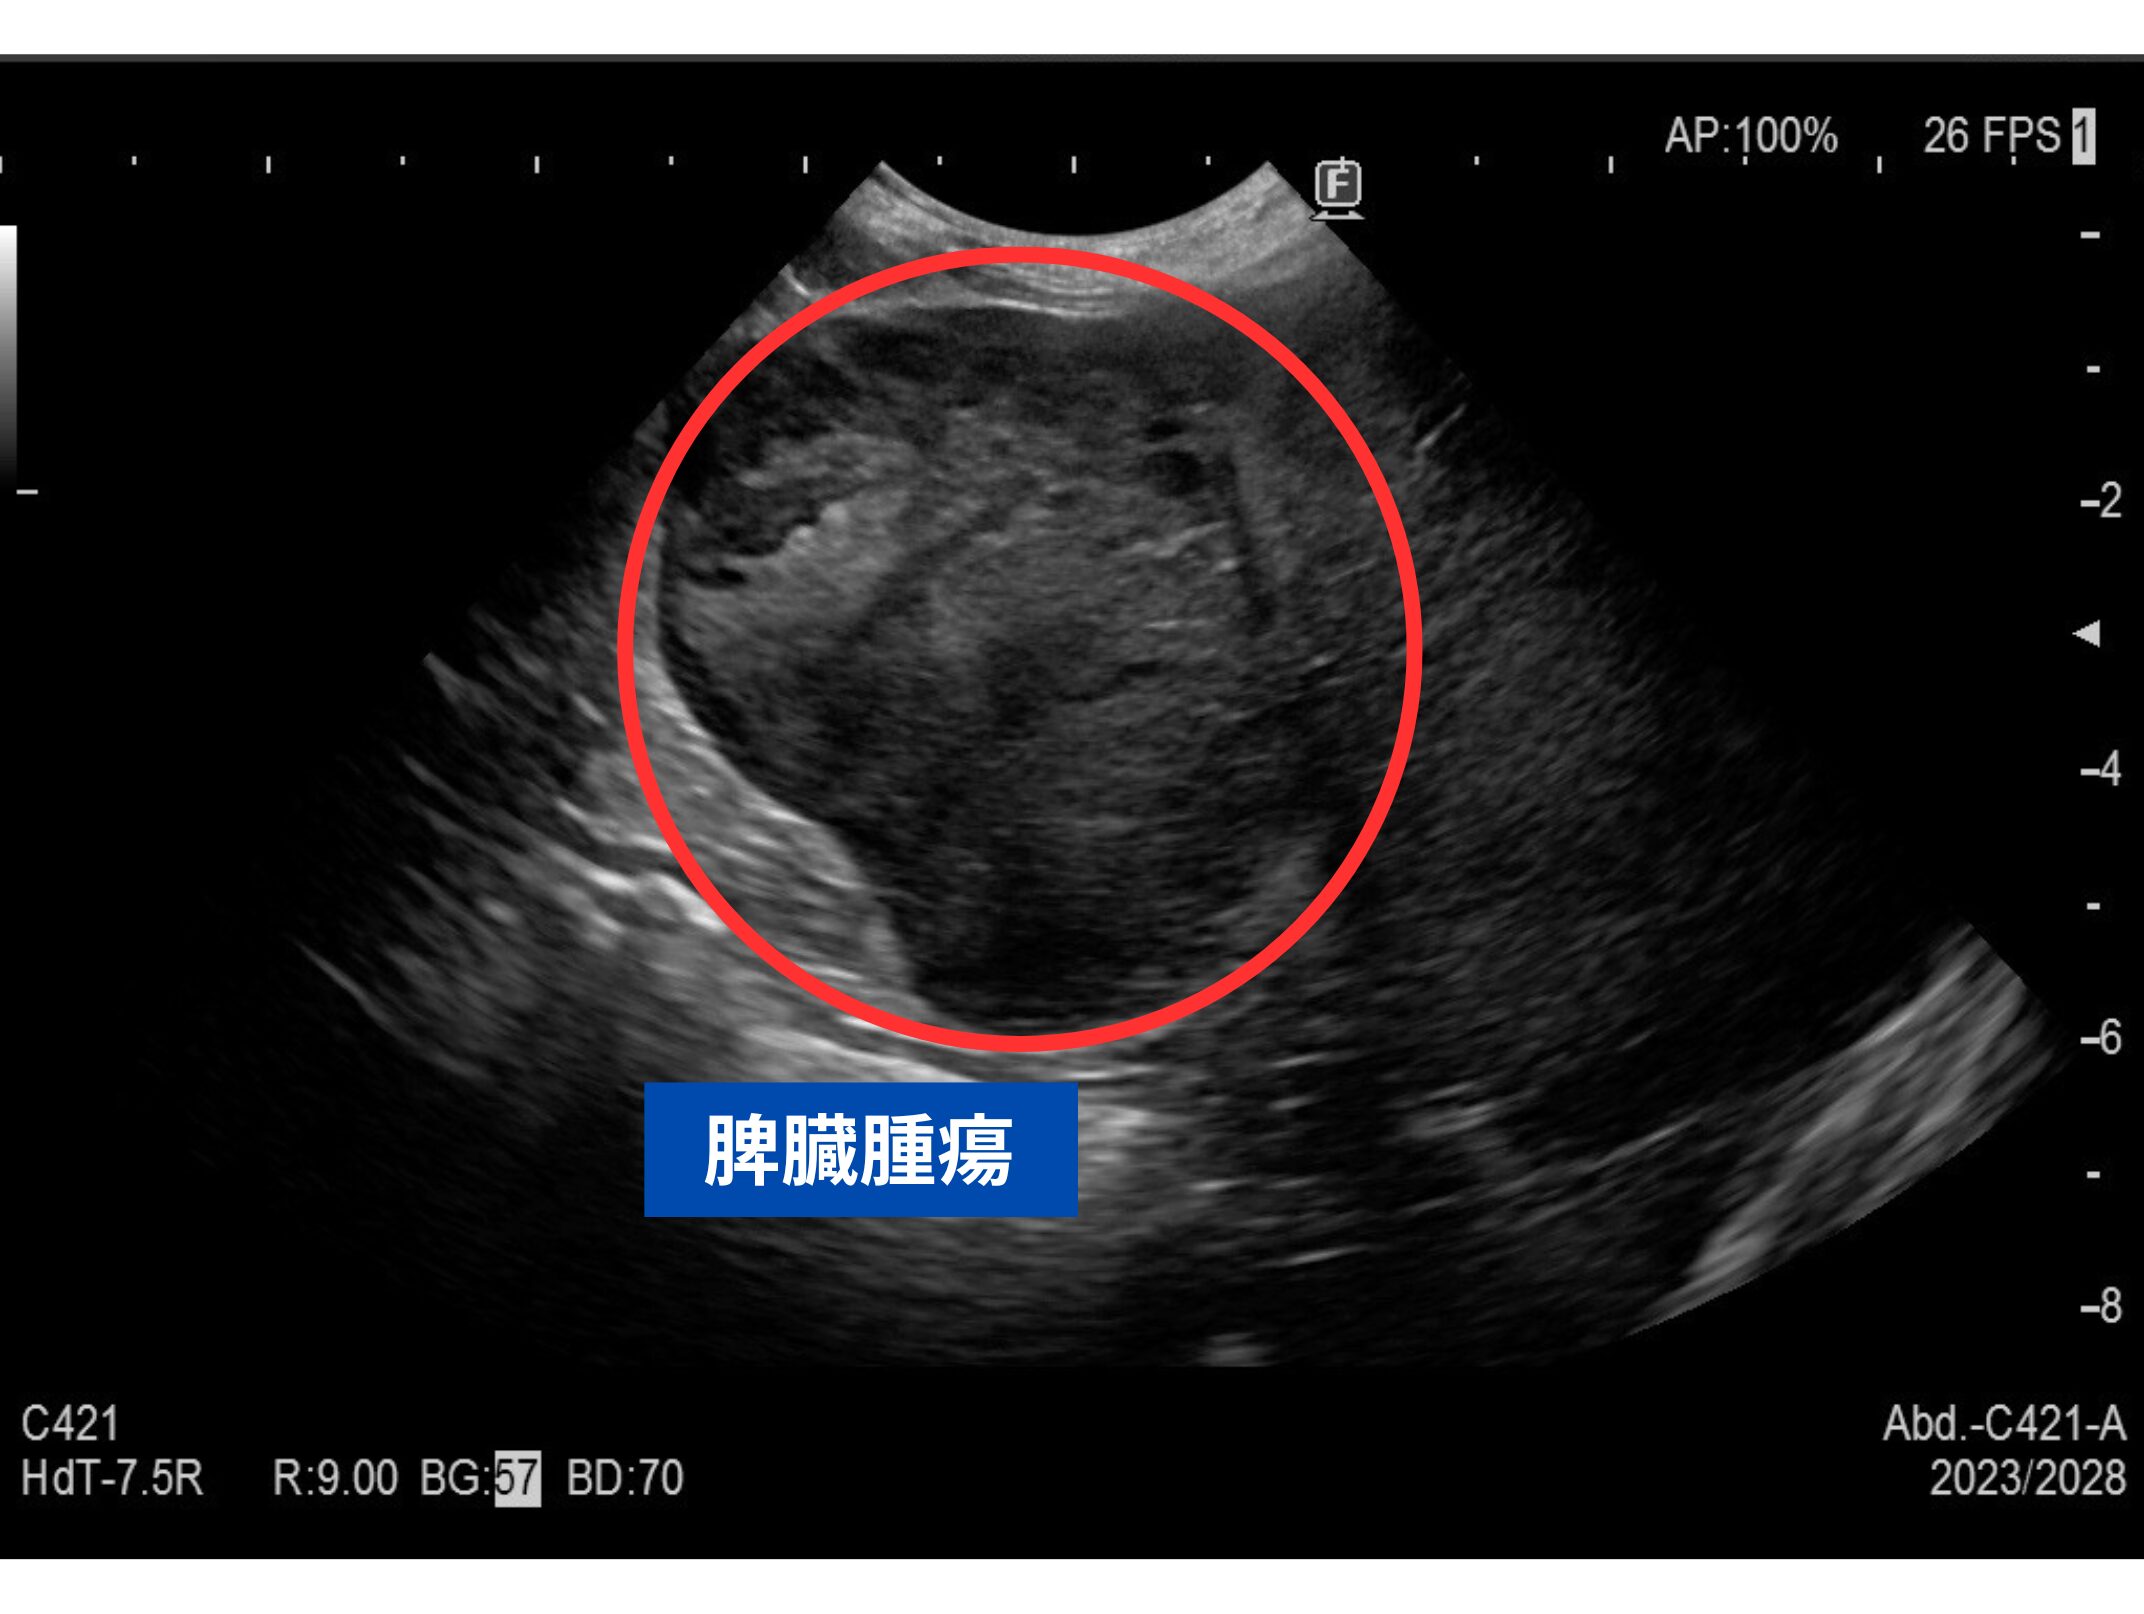

当院で腹部レントゲン検査と腹部超音波検査を実施したところ、脾臓に腫瘍性病変が確認され、腫瘍の破裂による腹腔内出血が疑われました。

次の画像が検査時の腹部レントゲン画像と超音波画像です。